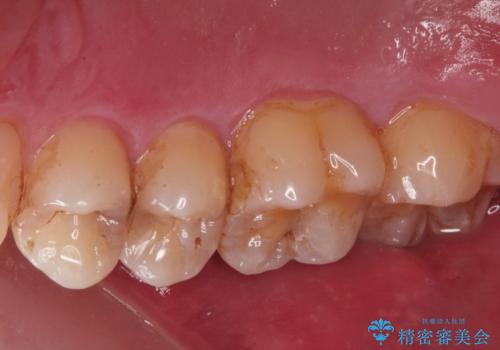

歯と歯の間の虫歯(コンタクトカリエス)

拡大鏡下で虫歯を全て除去して、e-maxインレーにて治療しました。

- e-maxインレー 7.7万円 費用は治療当時の料金となります